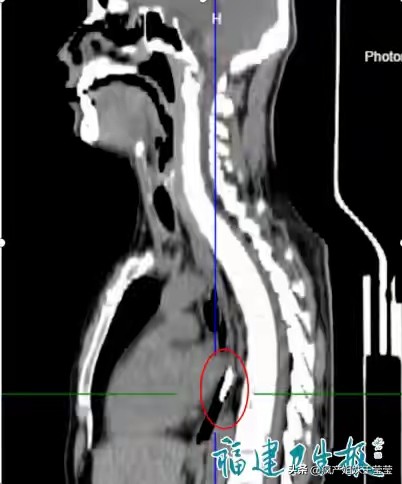

比硬币更危险的,是易燃易爆的硬物。一名36岁男子因情绪冲动,竟将一只完整打火机吞入腹中。CT显示打火机卡在食管下段,外壳坚硬光滑,一旦破损,易燃液体泄漏,可能灼伤消化道甚至引发爆炸。医生不敢大意,采用内镜+保护套的方式,小心翼翼将打火机完整取出,全程惊心动魄。这起案例警示我们,无论何种原因,都不能拿生命开玩笑,异物吞入体内,伤害无法预估。